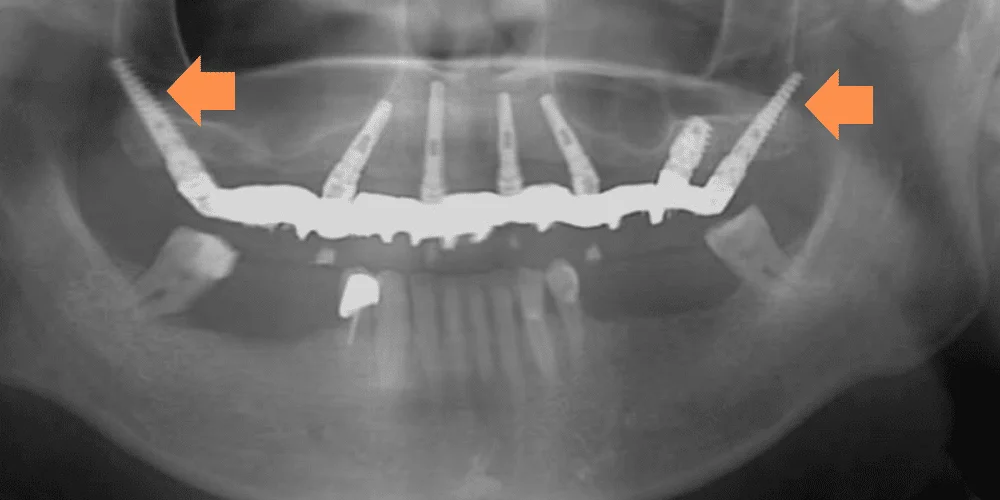

במידה והשתלת השיניים נעשית בשלבים מוקדמים של אובדן העצם ניתן עדיין להשתמש בעצם לעיגון השתלים ובכך גם להאט משמעותית את ספיגתה, אבל במקרים רבים שבהם ההשתלה נעשית תקופה ארוכה אחרי שהעצם החלה להיספג, אין מספיק עובי וכח לעצם הלסת כדי להחזיק את השתלים הדנטליים שרצינו להשתיל.

בעקבות המחסור בעצם הלסת העליונה אין למעשה לרופא השיניים מקום שאליו הוא יכול לעגן בצורה בטוחה את השתלים הדנטליים. לכן, עד להופעת שתלי הזיגומה הרופאים נאלצו למצוא פתרונות וטכניקות ש"ישלימו" את עצמות הלסת החסרות.

שתלים זיגומטיים הם למעשה שתלים דנטליים ייחודיים שנועדו להתמודד עם בעיית חוסר עצם בלסת העליונה, מבלי שיהיה צורך בהשתלת עצם או הליך מורכב כמו הרמת סינוס.

בשתלים רגילים, השתל מוברג לתוך עצם הלסת, שצלים זיגונטיים, לעומת זאת, הם שתלים ארוכים יותר משתלים רגילים ומגיעים אל מעל לאזור הלסת. כלומר אל עצם הזיגומה – העצם שממוקמת בחלק העליון של הלחי, היכן שנמצאת הגבעה של הלחי.

עצם הזיגומה היא עצם חזקה שנמצאת במיקום מדוייק מעל הפה שלנו ולכן מתאימה לעיגון של שתלים דנטליים.

בכך ניתן למעשה "לעקוף" את בעיית עצם הלסת החסרה, ללא טיפולים מייסרים של הרמות סינוס ולחסוך למטופלים ולמטופלות סבל רב וזמני החלמה ארוכים.